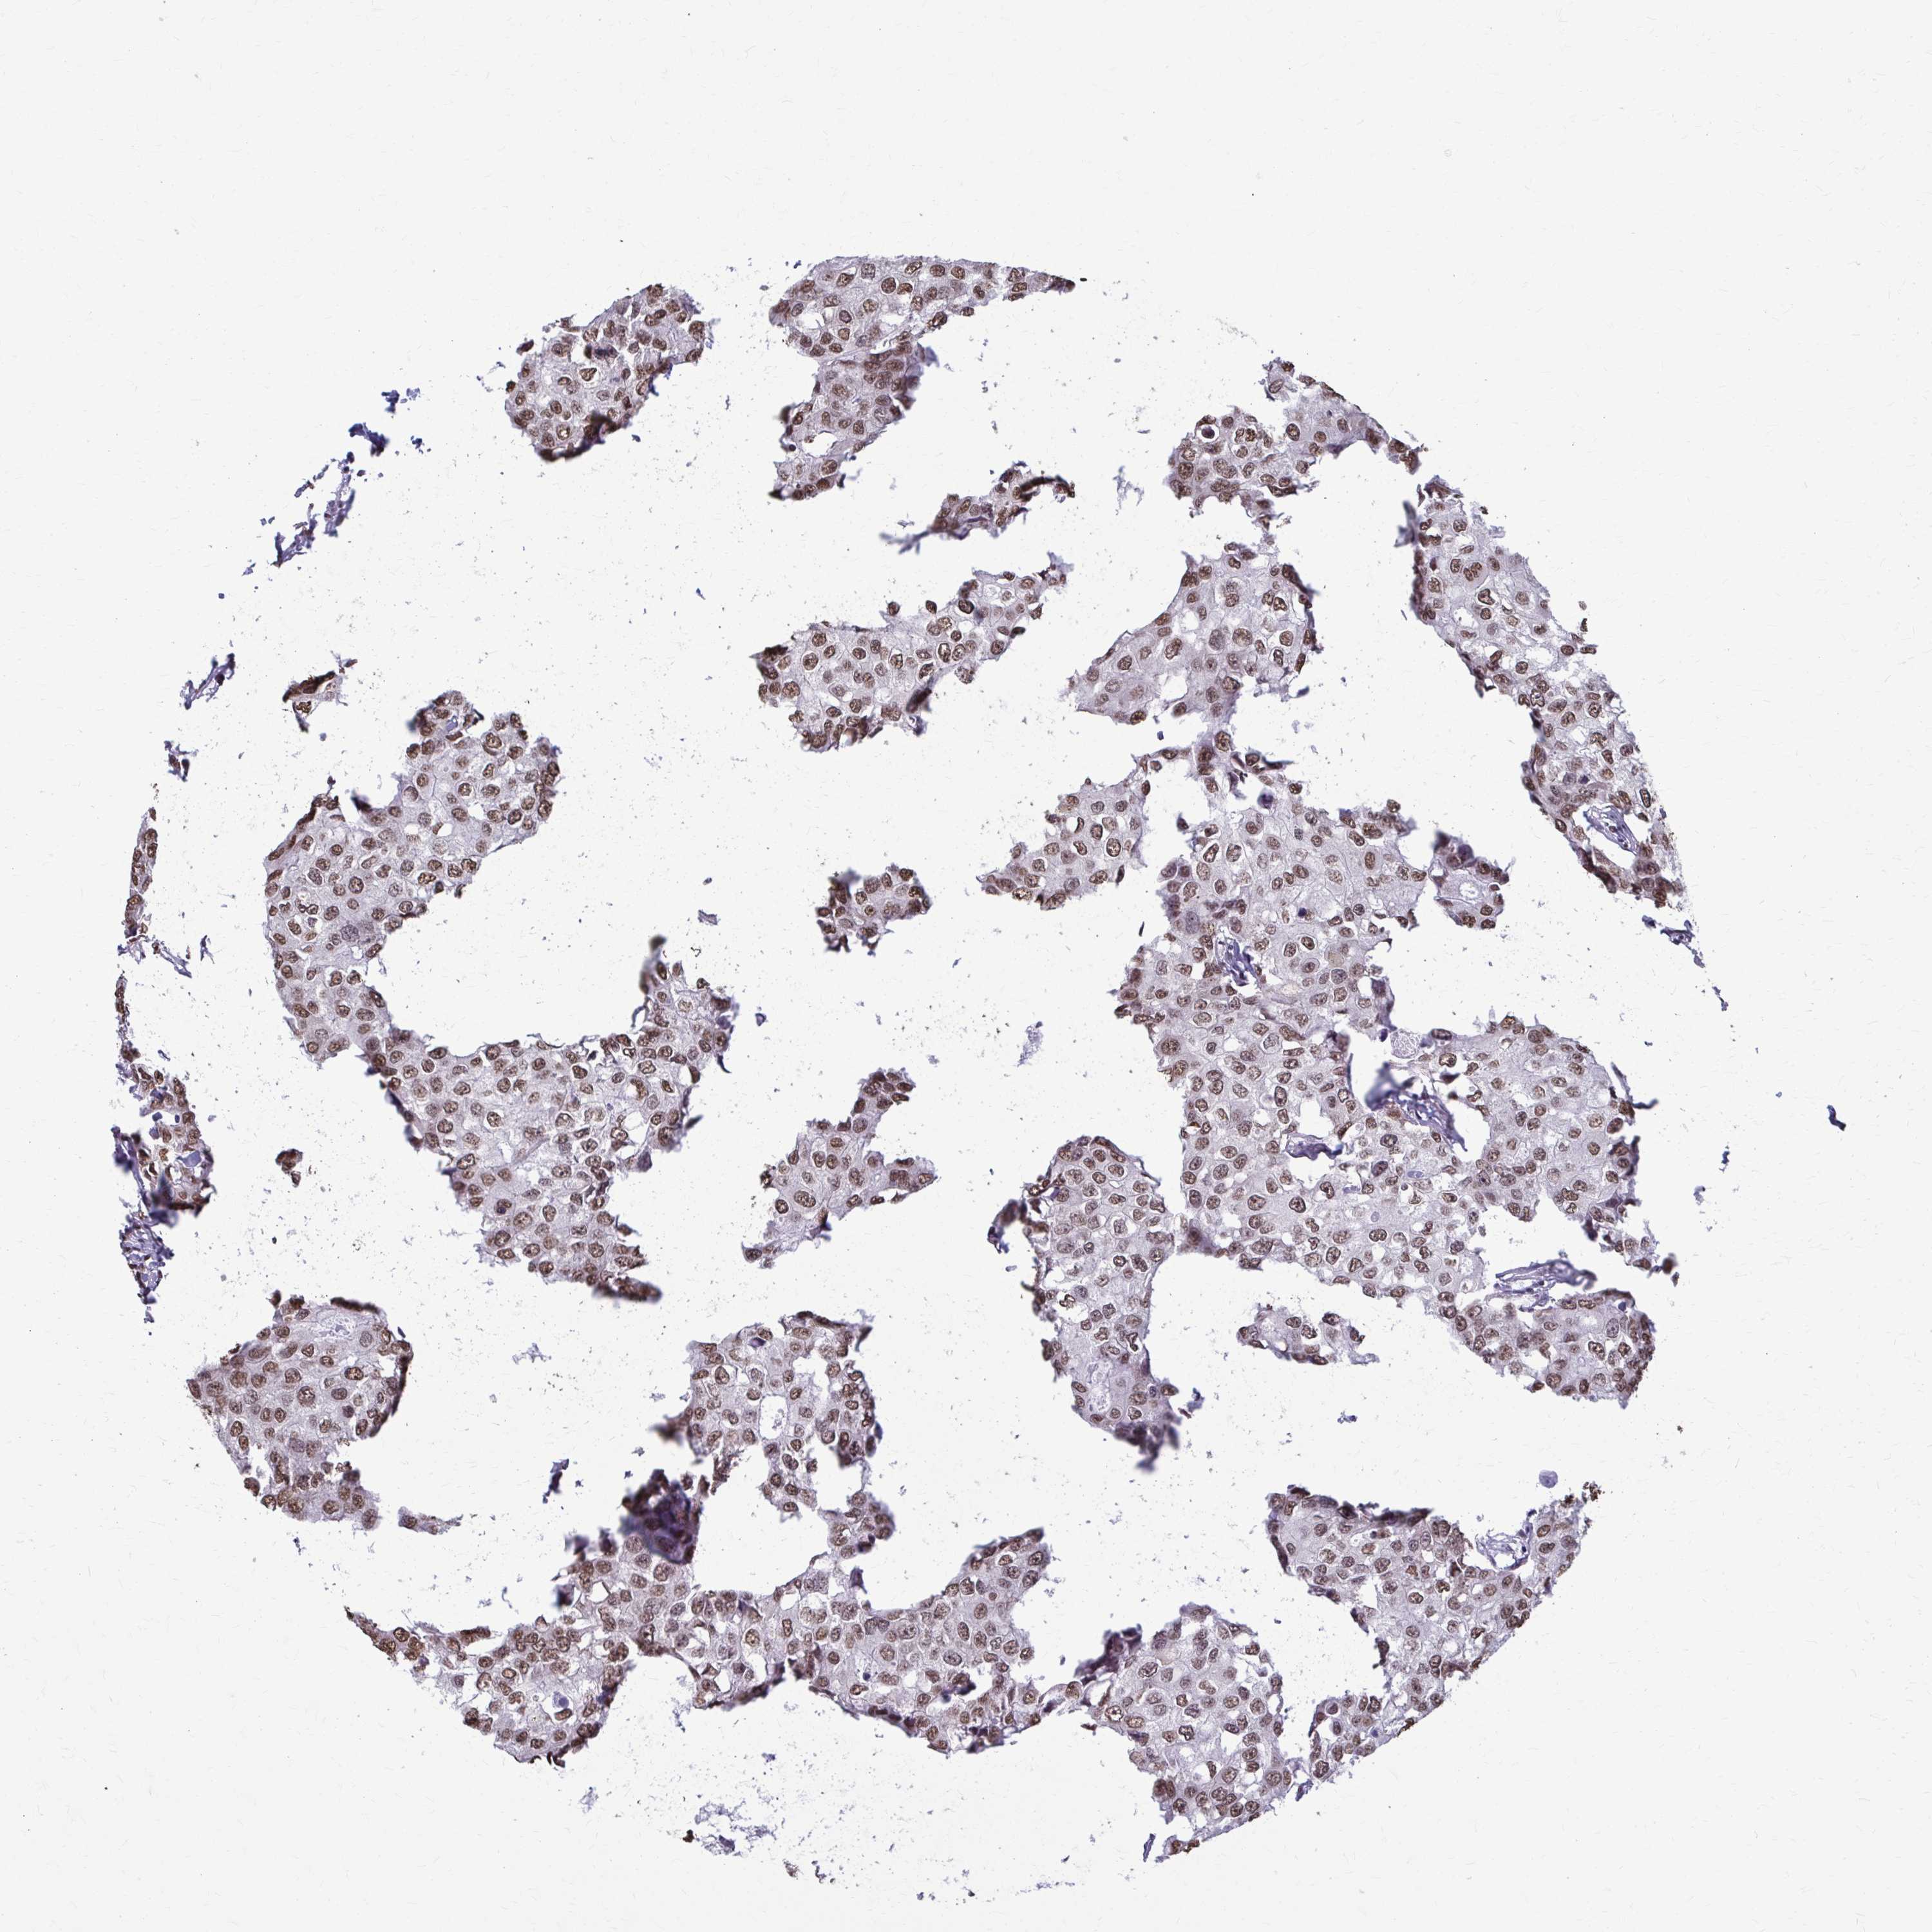

CANCER BREAST CANCER Show tissue menu

BRCA TCGA BRCA VALIDATION PROTEIN EXPRESSION